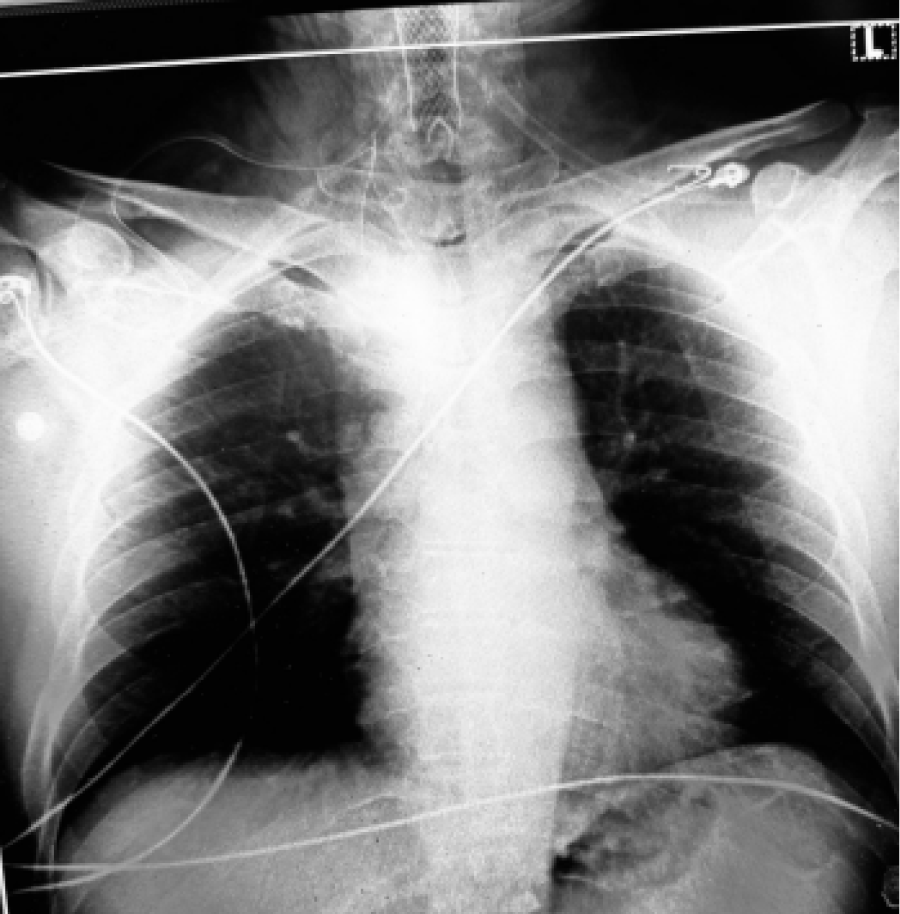

During the laser treatment, the tip of the fiberoptic tracheoscope was inadvertently slightly burned, but no additional tissue damage occurred on the patient. Bronchoscopy was subsequently performed to evaluate the extent of any injury, revealing no significant damage. Dexamethasone 8 mg IV was administered to minimize airway swelling. A tracheal stent was placed preoperatively to prevent tracheal stricture (Figure 2). After confirming adequate respiratory function and obtaining normal arterial blood gas values, the patient was transferred to the intensive care unit. He demonstrated stable recovery with no immediate complications and was discharged five days later.

Figure 2: The tracheal stent is seen in chest X-ray.